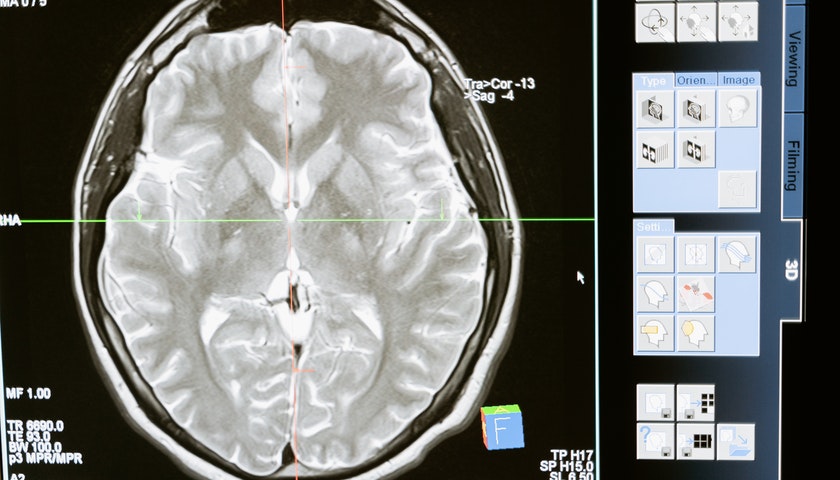

智能康复医疗器械正在从实验室走向市场,脑科学技术介入康复